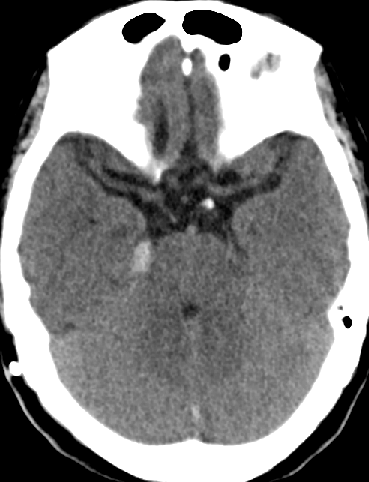

2015-3-31

脑压100

2015-4-1 MRI

诊断

脑膜癌?

特发性肥厚性硬脊膜炎?

进展性特发性肥厚性硬脊膜炎